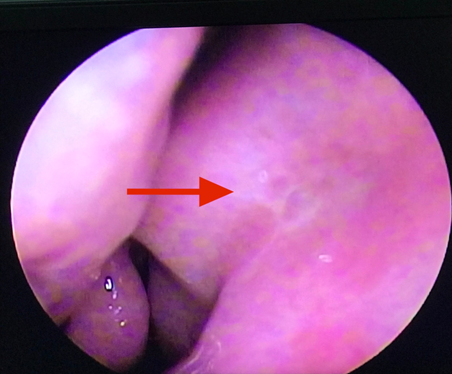

Vừa qua khoa Mắt - Bệnh viện Đa khoa tỉnh vừa tiếp nhận vầ điều trị Bệnh nhân nữ 49 tuổi vào viện vì xuất hiện khối sưng nề góc trong mắt trái kết hợp chảy mủ và chảy nước mắt nhiều. Tại đây bệnh nhân được xác định chẩn đoán Mắt trái: Viêm mủ túi lệ/ Tắc lệ đạo, bệnh nhân đã được điều trị nội khoa tích cực, triệu chứng lâm sàng giảm dần. Khoa Mắt và khoa Tai mũi họng đã kết hợp phẫu thuật cho bệnh nhân bằng phương pháp Nối thông túi lệ mũi bằng nội soi. Phẫu thuật này đã tạo đường thông trực tiếp từ túi lệ sang khoang mũi nhằm dẫn nước mắt từ mắt sang mũi. Sau phẫu thuật 2 ngày, các triệu chứng lâm sàng của bệnh nhân thuyên giảm và được ra viện sớm.

Hình 1. Xác định vị trí phẫu thuật